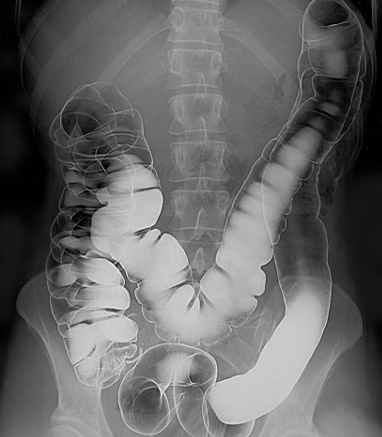

Le lavement baryté est une injection rectale de produit de contraste baryté. Celui-ci recouvre la paroi du côlon et du rectum et des radiographies sont obtenues sous contrôle fluoroscopique. De l'air introduit dans le gros intestin peut être utilisé pour obtenir une technique de double contraste. Les lavements au baryum sont pratiqués beaucoup moins souvent que par le passé en raison de l'utilisation croissante de la coloscopie et de la colonographie par tomodensitométrie.

Lavement baryté du tractus intestinal

© Glitzy queen00 at English Wikipedia., Public domain, via Wikimedia Commons

Par Glitzy queen00 at English Wikipedia, Public domain, via Wikimedia Commons

Le baryum est introduit dans le côlon par gravité et des radiographies sont prises. De l'air est également introduit dans le rectum pour un lavement baryté à double contraste.